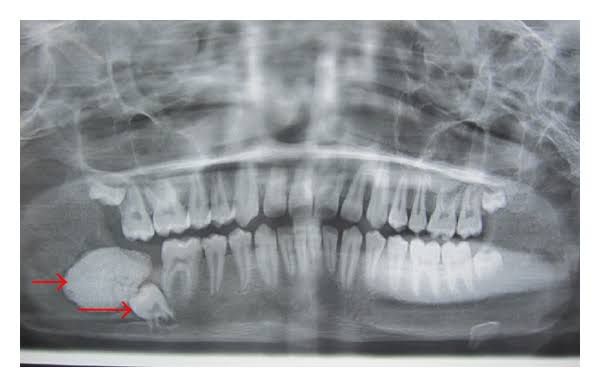

Complex odontoma is a common odontogenic tumor, and it is usually a hard painless mass, which rarely exceeds diameter of the tooth. Most of these lesions are discovered accidentally on radiographic examination. The common signs and symptoms include impacted permanent teeth and swelling.